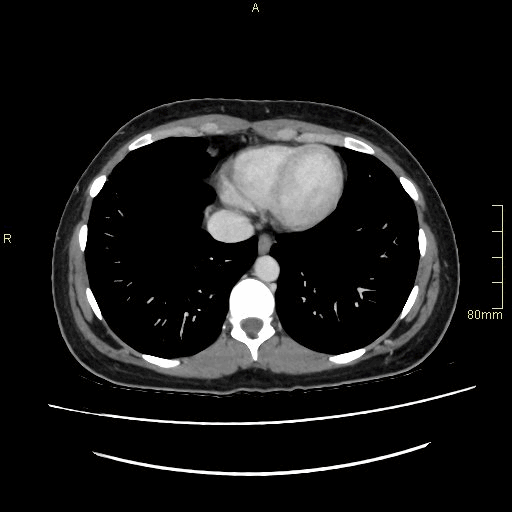

CT Abdomen Venogram- Soft tissue window (sagittal)